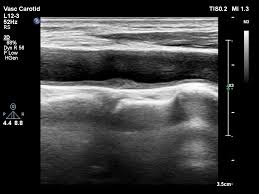

검사 결과에서 주로 보는 지표

판독 시 중요한 평가 항목은 다음과 같습니다.

- 플라크 위치와 크기

- 협착률(혈관이 얼마나 좁아졌는지 퍼센트로 표시)

- IMT 수치(혈관 노화 및 동맥경화 지수)

- 혈류 속도 증가 여부

- 혈전 또는 혈관 박리 여부

결과 수치는 뇌졸중, 심근경색 예방 전략 수립에 직접적으로 영향을 줍니다.